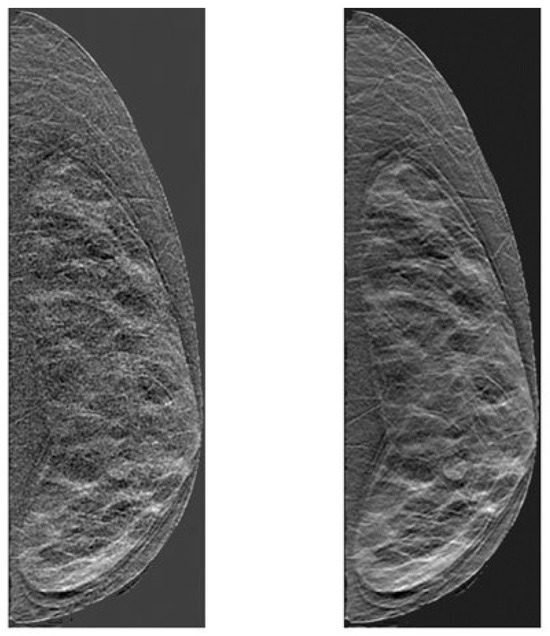

2. Materials and Methods

2.3. Clinical Data

3.3. Breast Density